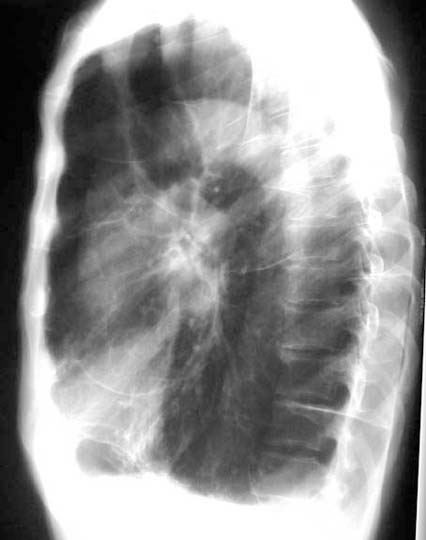

Lateral

Labeled Image

What are the contents of a cavity?